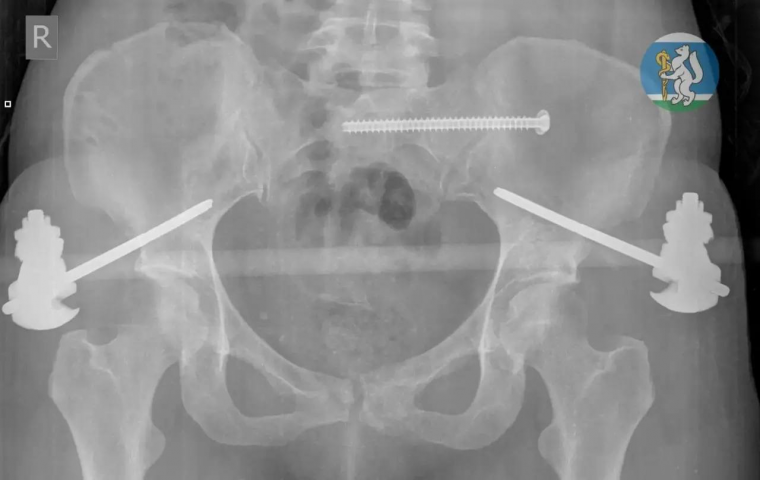

В состоянии тяжелейшего травматического шока женщину доставили в реанимацию. Диагнозы звучали как приговор: черепно-мозговая травма, повреждение позвоночника, множественные переломы таза, открытые переломы ноги. Большинство пациентов с такими травмами умирают еще до приезда скорой. Но здесь, в 36-й, за дело взялась команда: хирурги, травматологи, нейрохирург, реаниматолог. Несколько часов они буквально вырывали пациентку с того света.

Спасали поэтапно. Сначала — реанимация, борьба за каждое сердцебиение. Затем — стабилизация, когда организм, переживший шок, наконец перестал сдаваться. И наконец — серия сложнейших операций, каждая из которых могла стать последней. Операционная превратилась в поле боя, где врачи сражались не с абстрактной болезнью, а с травмами, которые обычно оставляют на теле лишь память о погибшем.